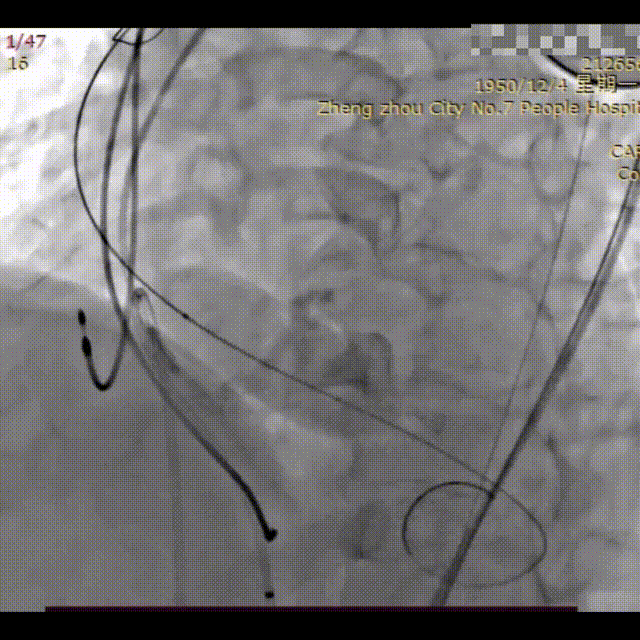

手术过程概览:

冠脉造影